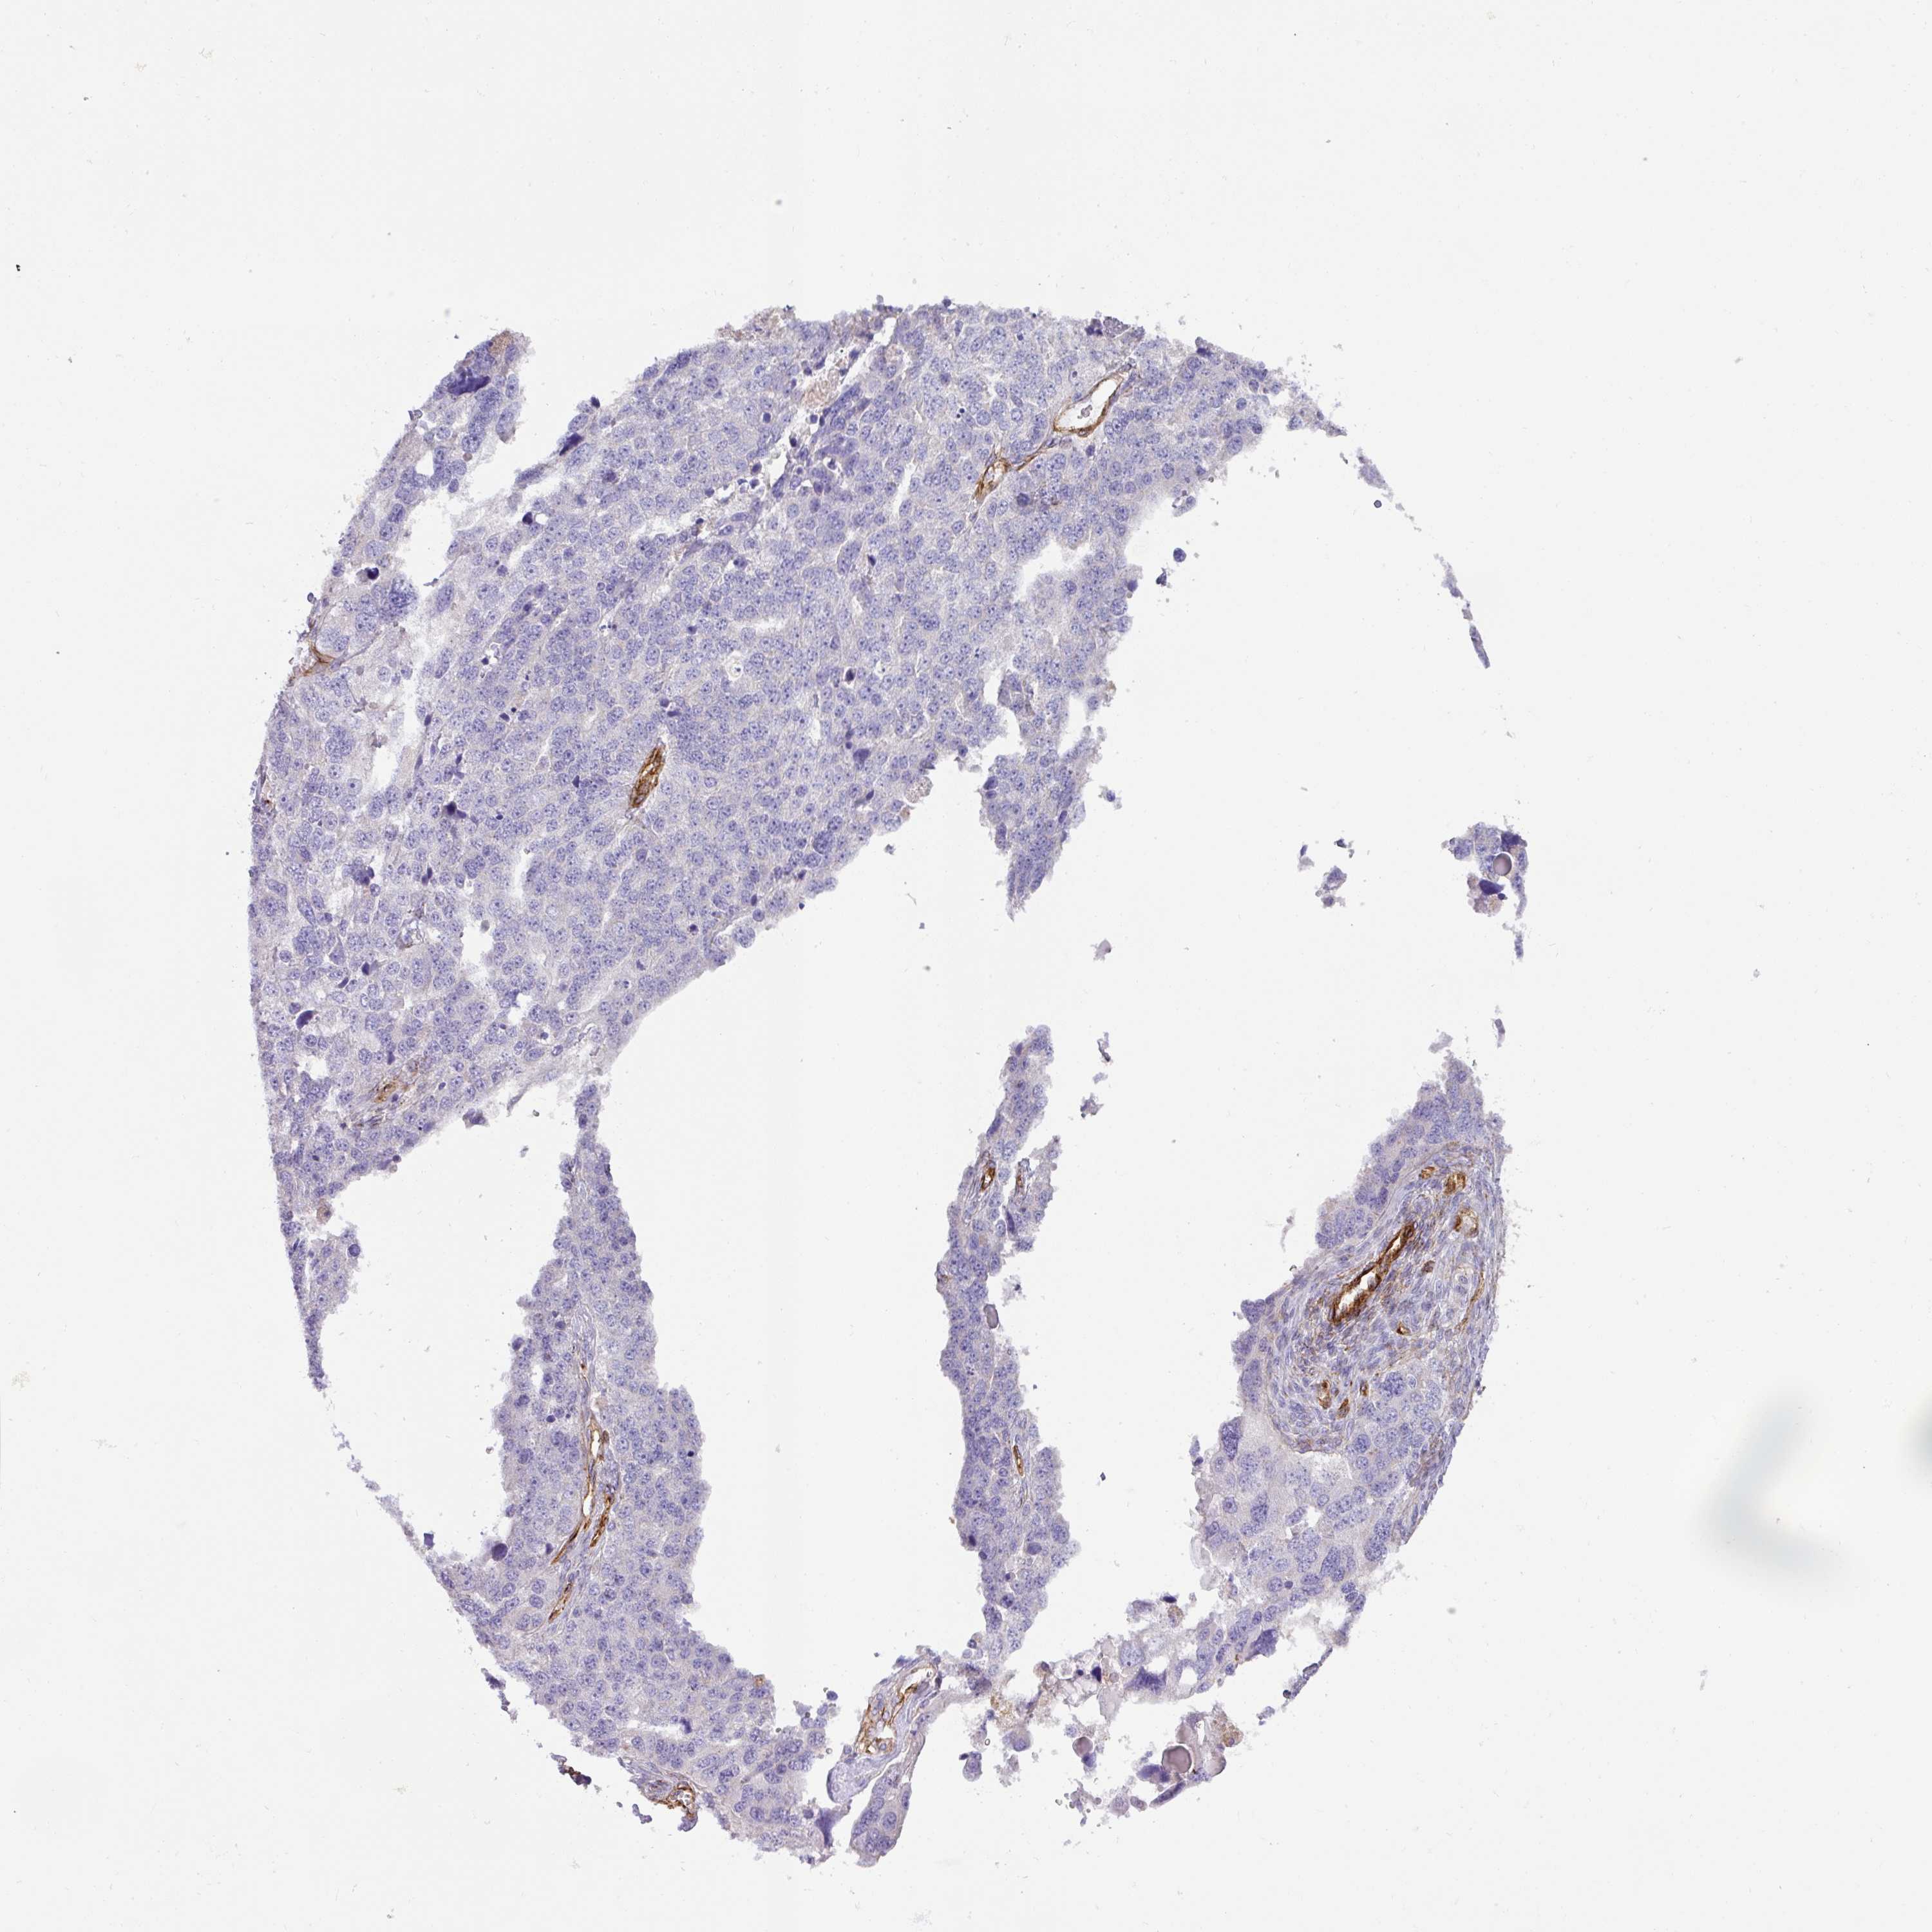

OVARIAN CANCER - Protein expressioni

A mouse-over function shows sample information and annotation data. Click on an image to view it in a full screen mode. Samples can be filtered based on level of antibody staining by selecting one or several of the following categories: high, medium, low and not detected. The assay and annotation is described here.

Note that samples used for immunohistochemistry by the Human Protein Atlas do not correspond to samples in the TCGA dataset.

Antibody stainingi

Antibody staining in the annotated cell types in the current human tissue is reported as not detected, low, medium, or high, based on conventional immunohistochemistry profiling in selected tissues. This score is based on the combination of the staining intensity and fraction of stained cells.

Each image is clickable and will lead to virtual microscopy that enables deeper exploration of all samples and also displays staining intensity scores, fraction scores and subcellular localization as well as patient and tissue information for each sample.

Antibody HPA052708

Staining

High

Medium

Low

Not detected

Intensity

Strong

Moderate

Weak

Negative

Quantity

>75%

75%-25%

<25%

None

Location

Nuclear

Cytoplasmic/membranous

Cytoplasmic/membranous,nuclear

Cystadenocarcinoma, serous, NOS

Cystadenocarcinoma, mucinous, NOS

Adenocarcinoma, NOS

Carcinoma, endometroid